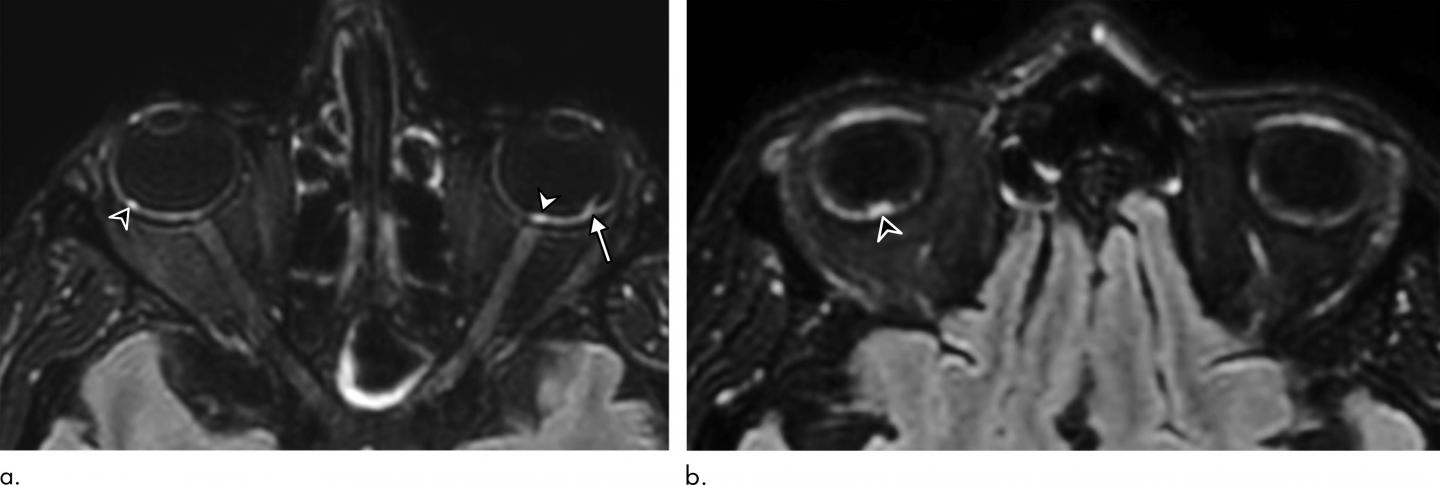

Of the 129 patients, nine (7%) had abnormal MRI findings of the globe, or eyeball. The MRI scans showed one or more nodules in the back part, or posterior pole, of the eyeball. Eight of the nine patients had spent time in the intensive care unit (ICU) for COVID-19.

All nine patients had nodules in the macular region, the area in the back of the eye responsible for our central vision. Eight had nodules in both eyes.